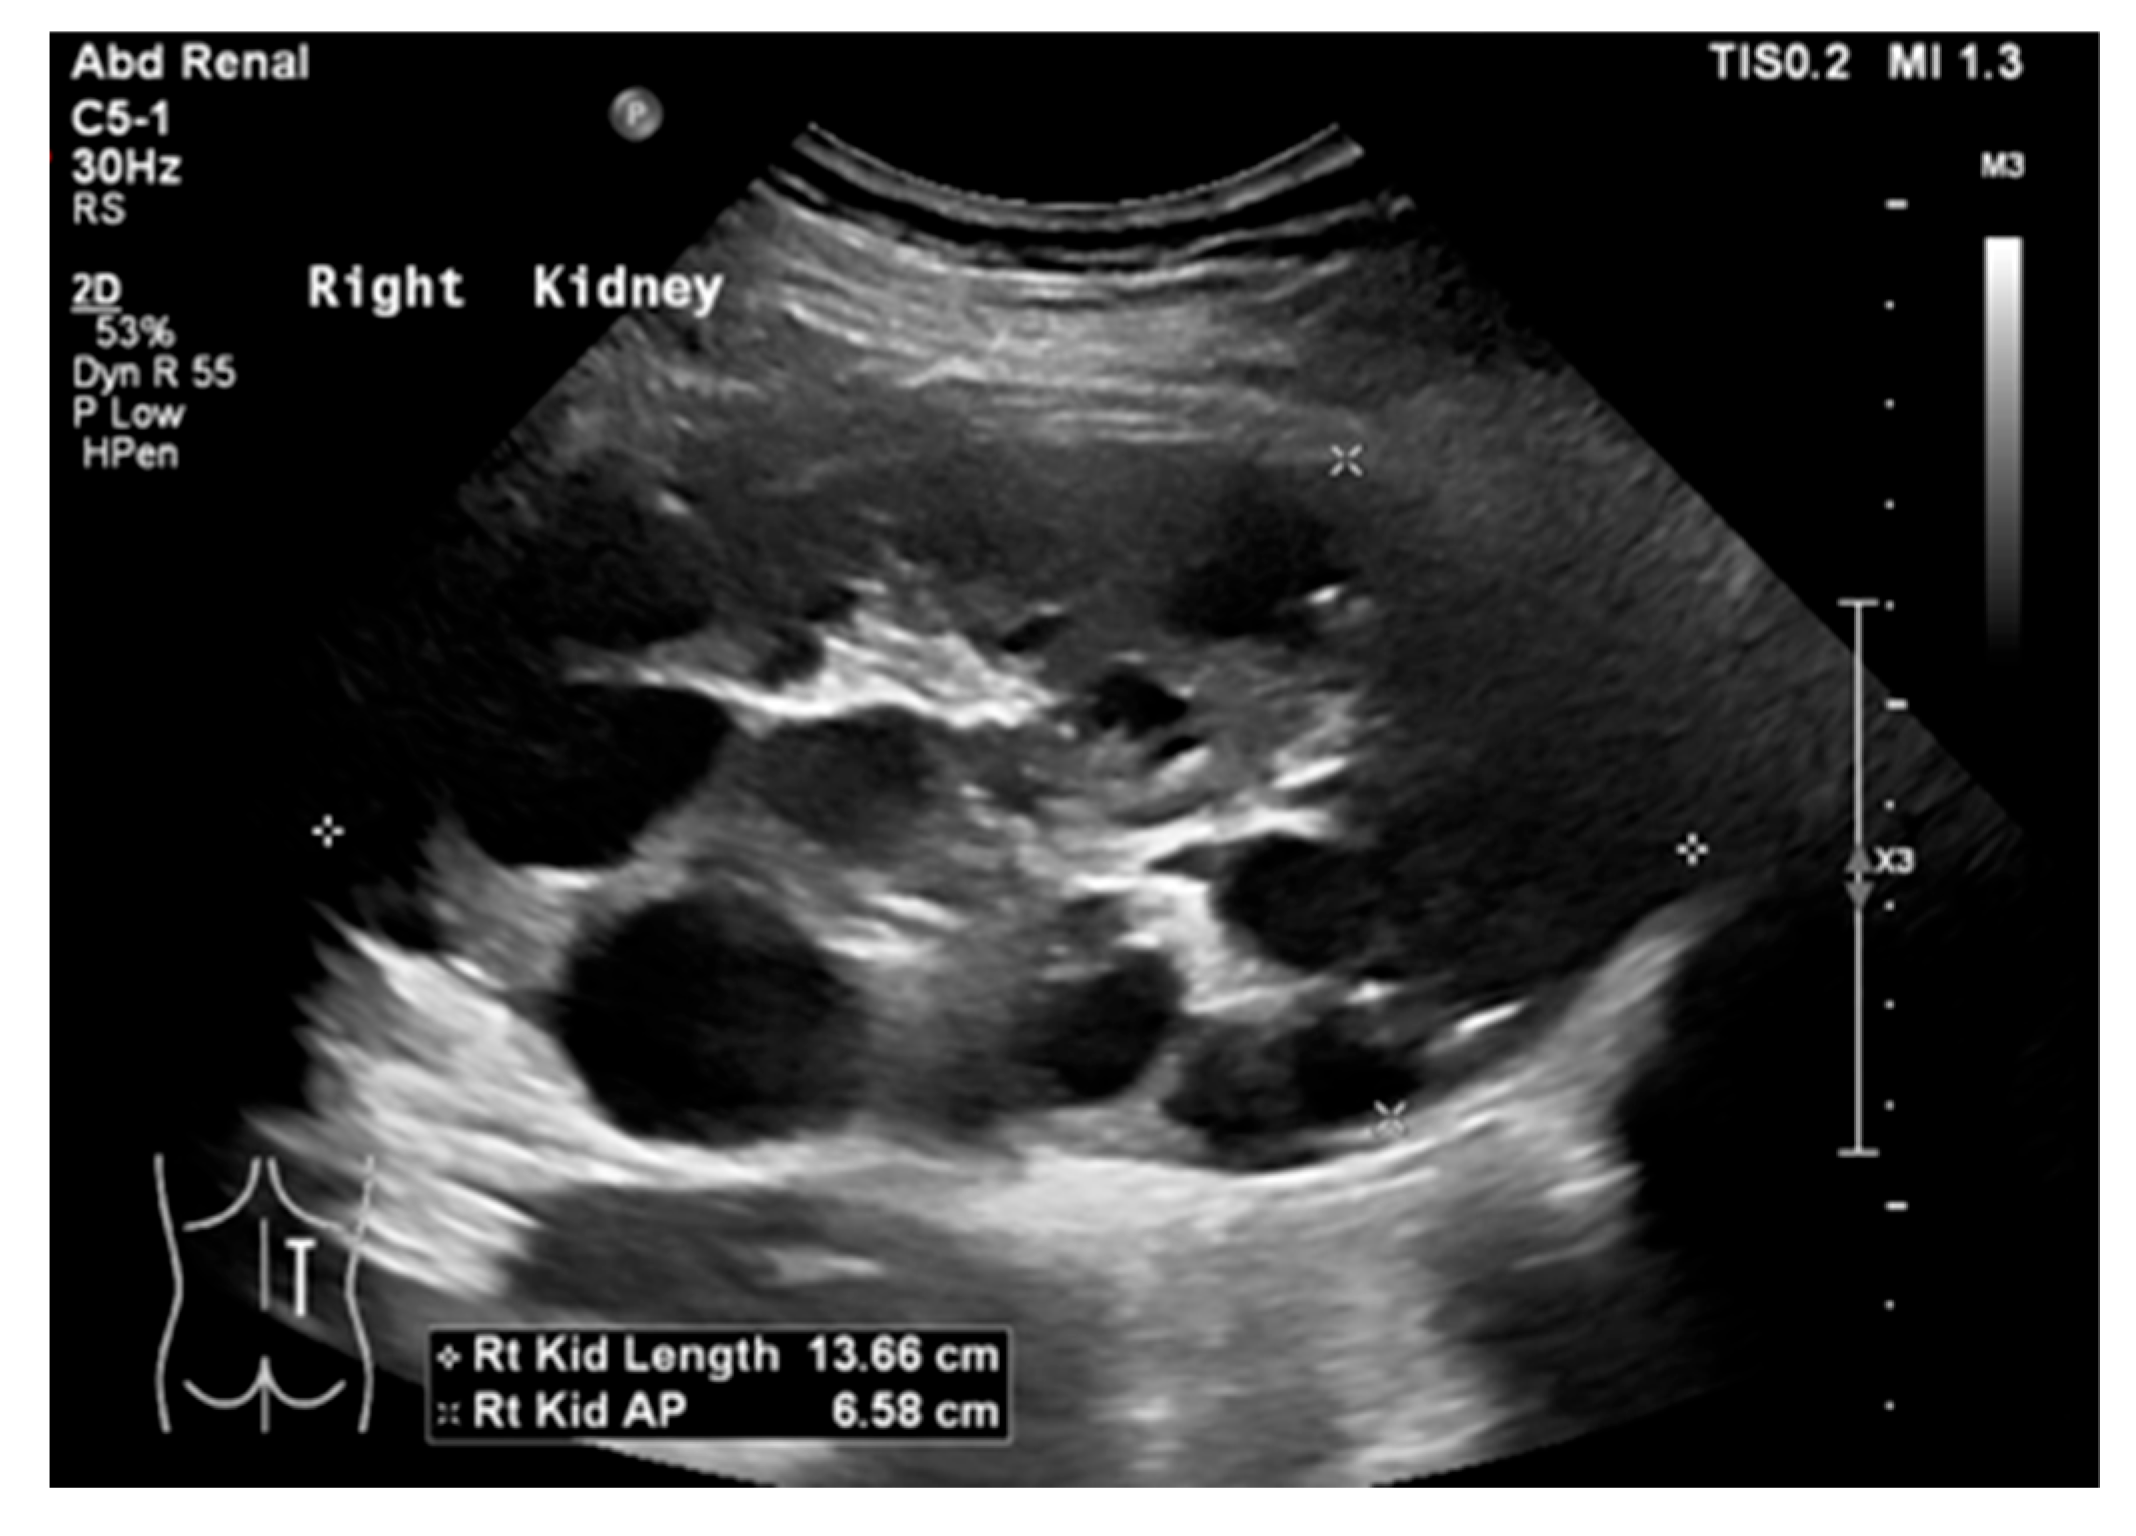

Autosomal recessive polycystic kidney disease (ARPKD) presents with a broad clinical spectrum, from severe perinatal forms to minimal renal disease with dominant hepatic fibrosis. Ultrasound (US) is the initial diagnostic tool, typically showing enlarged, echogenic kidneys with poor corticomedullary differentiation. Microcysts are not visible on US, but macrocysts may be seen in older children (Figure 18) [65,66,67].

Figure 9. (a) US shows right MCDK in a 23-month-old male. (b) Renal scan shows no uptake in the right kidney.

Medicina 61 00696 g009